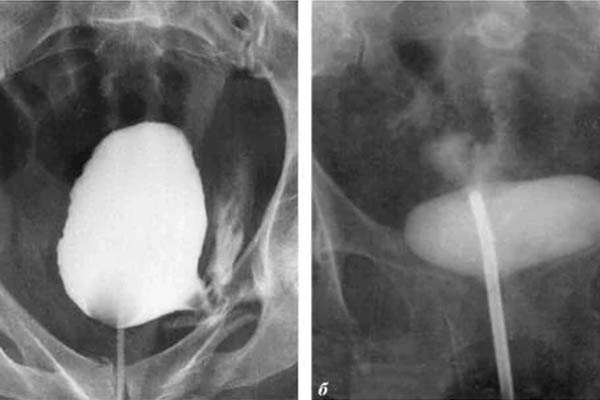

Saya ingin menunjukkan beberapa foto tentang apa yang terjadi pada sistem genitourinari dan organ dalam lainnya dari seorang pria ketika dia berhenti berhubungan seks.

Seperti inilah peradangan prostat karena stagnasi di dalamnya (dengan tidak adanya pengosongan testis, yang terjadi saat berhubungan seks). Peradangan yang berkepanjangan pertama-tama mengarah ke adenoma, dan kemudian ke kanker prostat (dari mana, menurut statistik, 38% pria meninggal). Dengan tidak adanya seks, ini selalu terjadi, itulah sebabnya adenoma dianggap sebagai penyakit orang tua.